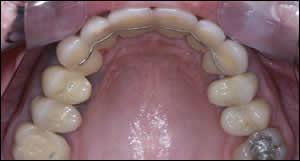

Fig 9: Nickel titanium wires with Tip-Edge brackets provided rapid leveling and unraveling of the incisors with light force.

Fig 10: A coil spring was used to position tooth # 7 equidistant between tooth #6 and 8. An elastic chain was utilized on the lower arch to close the space that was created by uprighting tooth #24 and 26. Note tooth #25 is missing.